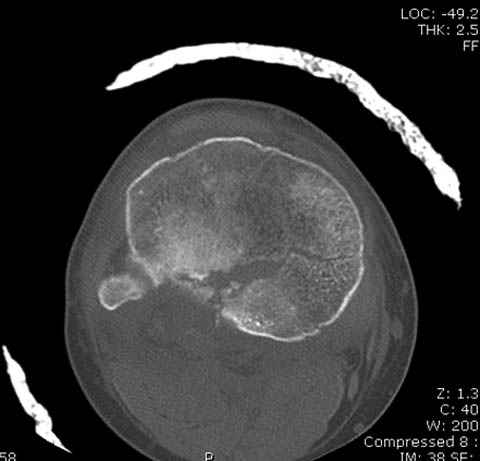

На представленных предоперационных срезах КТ огромный задне-медиальный фрагмент расположен больше кзади, чем медиально. Для планирования, кроме поперечных срезов, надо ориентироваться на корональные срезы, которые укажут топографию верхушки медиального фрагмента.